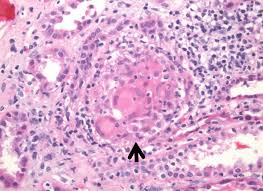

1. Granulomatous Interstitial Nephritis

Granulomas form in the kidney tissue, causing inflammation and scarring that interferes with the kidneys’ ability to filter waste.

- Kidney biopsy: may be required to confirm granulomas